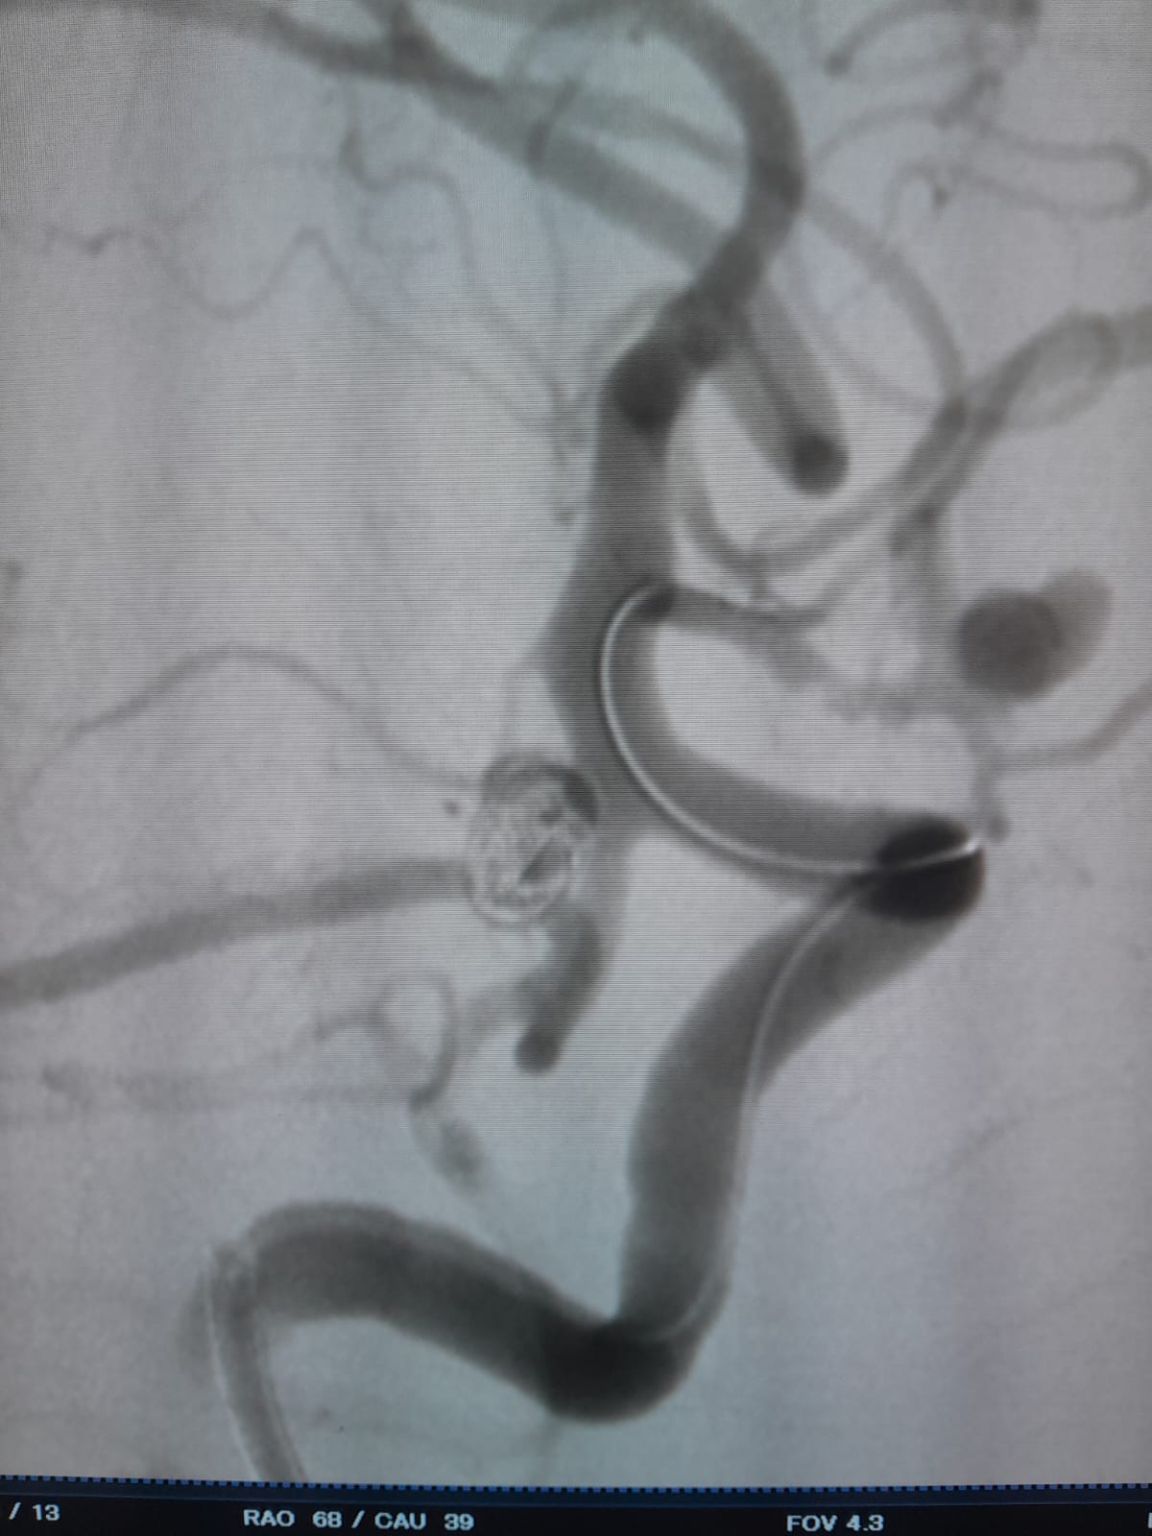

The patient was diagnosed with a newly discovered anterior communicating artery (AComA) saccular aneurysm and a posterior communicating artery (PComA) aneurysm that had been previously treated with coil embolization. Follow-up imaging revealed residual filling in the PComA aneurysm, requiring additional intervention.

During follow-up, residual filling was noted in the previously treated posterior communicating artery aneurysm. The team re-accessed the site using Frepass® Disposable Microcatheter (TJMC18 Plus) and successfully deployed a Nuva® Flow Diverter (TJED-D-4.5-16), which demonstrated ideal wall apposition and excellent flow diversion, leading to highly satisfactory treatment outcomes.